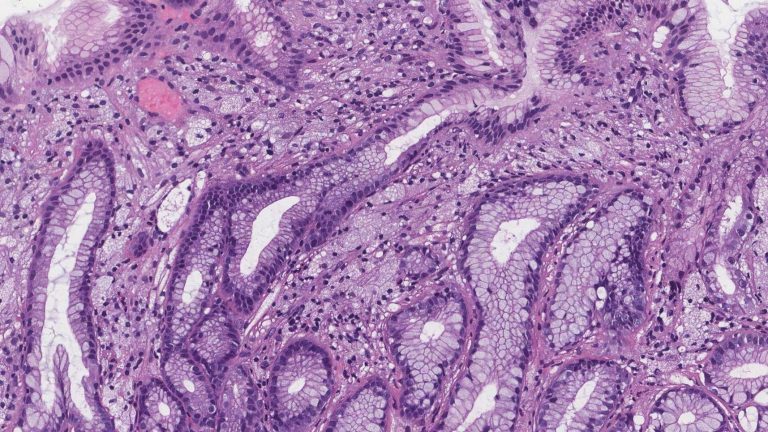

Ксантом буюу арьсны шар гүвдрүү

Xanthomas (yellowish plaques under the skin) (english)

Ксантома (желтоватые бляшки под кожей) (ру́сский)